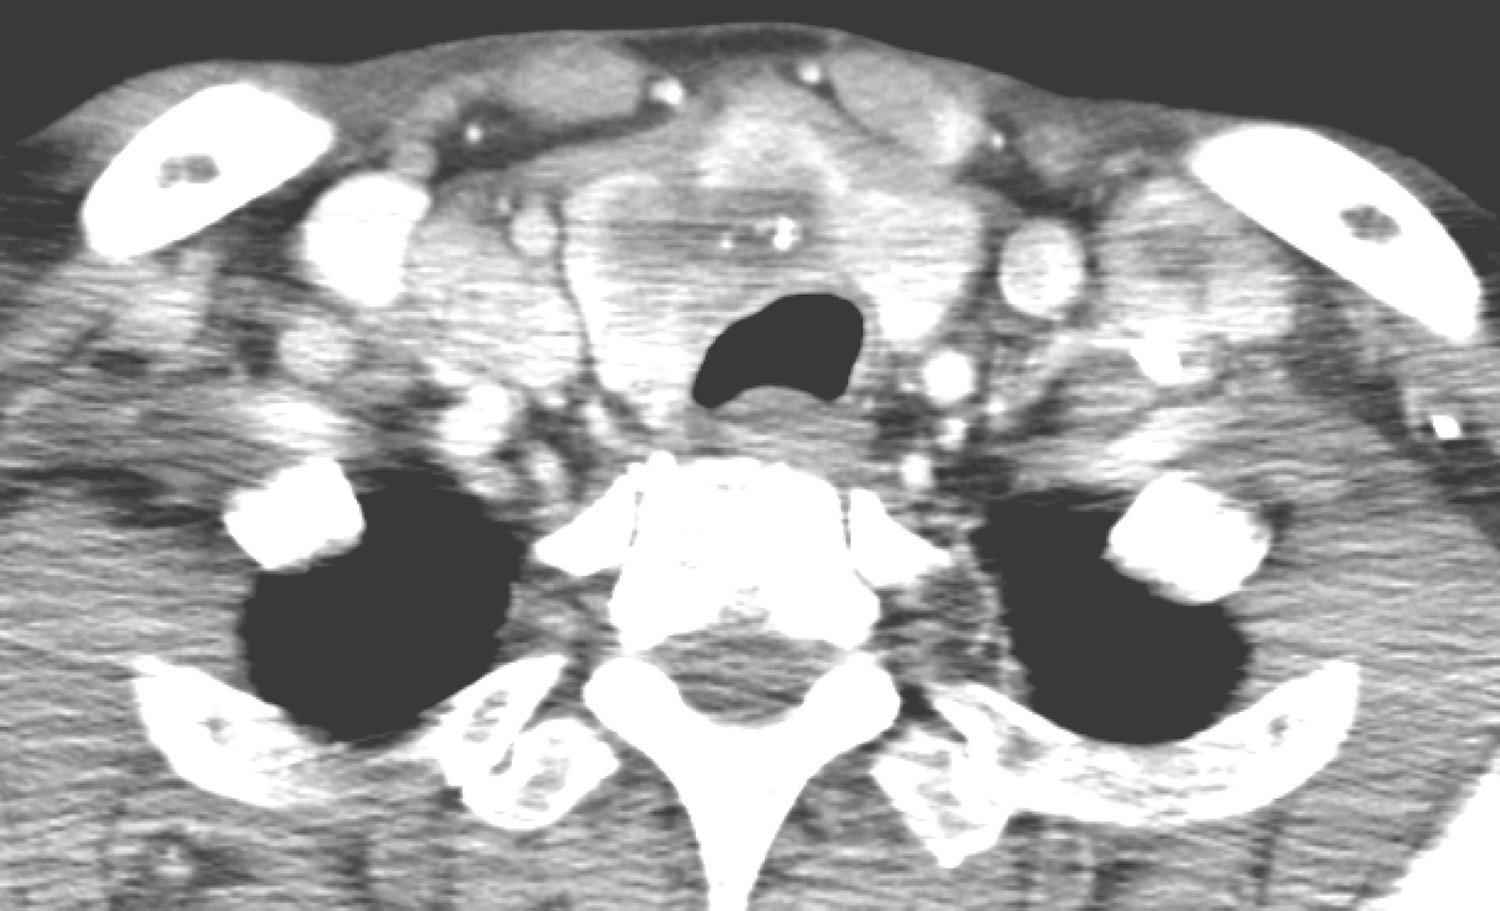

甲状腺形态饱满,峡部及右叶可见低密度结节,边缘不规则,最大截面约2.3cm×3.3cm,伴钙化,结节与气管关系密切。左侧甲状腺内亦可见密度略低区域,具体范围难以确定(图1)。

图1 颈部增强CT示甲状腺峡部及右叶低密度结节,左侧甲状腺内亦可见密度略低区域